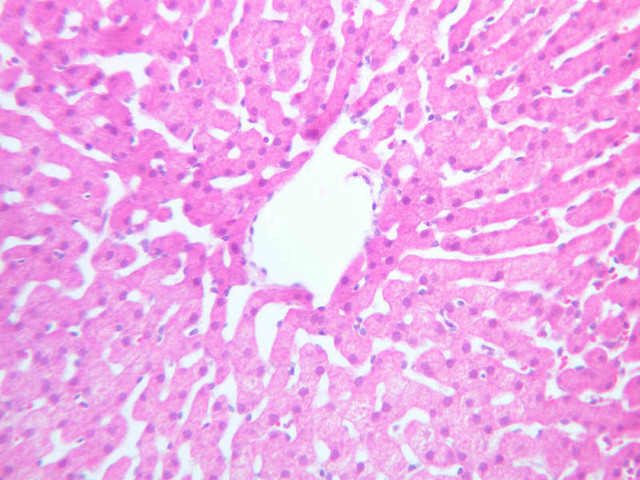

Examine the H&E-stained sections of liver (slides B-29 [10x, 20x, 40x-labeled] [2.5x-labeled, 10x, 20x, 40x] [10x-labeled, 20x, 40x-labeled] and B-30 [2.5x, 10x-labeled, 20x]). At low power, identify the connective tissue capsule (Glisson’s capsule), central veins and portal triads (portal canals). Note that the cells of the liver parenchyma (hepatocytes) appear as cords--more accurately, plates--of cells that radiate out from the central veins and partially enclose blood spaces known as hepatic sinusoids. Note that the plates of hepatocytes appear to branch and fuse and that, as a rule, they are only one or two cells thick. Do you see any binucleate hepatocytes?

Using the 10X (B-29, B-30)and 40X (B-29) objectives, examine several portal triads, noting the variable number of profiles of hepatic artery, portal vein and bile duct that comprise the portal triad. Near the boundary between adjacent lobules, try to find some of the small elements of the bile duct system known as canals of Hering.

Using the high dry objective, study the lining of the central vein and hepatic sinusoids (B-29). In some places the hepatocytes are exposed directly to the sinusoidal lumen, but, as a rule, there is a basal lamina which supports a discontinuous mosaic of endothelial cells and specialized phagocytic cells known as Kupffer cells. Find examples of Kupffer cells and endothelial cell nuclei. Note that in some places you may see a narrow space (the space of Disse) between hepatocytes and the basement membrane underlying endothelial and Kupffer cells. Using the oil immersion (100X) objective, look very carefully along the boundaries between adjacent hepatocytes to see if you can find a bile canaliculus--the most delicate portion of the bile duct system--the walls of which are formed by the plasma membranes of adjacent hepatocytes.

(1) Identify the portal triads that define the boundaries of a “classic” liver lobule (B-29). Since it surrounds a central vein, the classic lobule may be thought of as emphasizing the endocrine functions of the liver.

(3) A liver acinus is roughly elliptical in section. Its shorter axis (equator) is defined by the terminal branches of the hepatic artery and portal vein, which course along the boundary between adjacent classic lobules; its longer axis is defined by the two central veins nearest the equator (B-29). Although it is more difficult to visualize a liver acinus than a classic or portal lobule, the concept of acinar organization is very useful because certain features of liver metabolism best fit the acinar model.